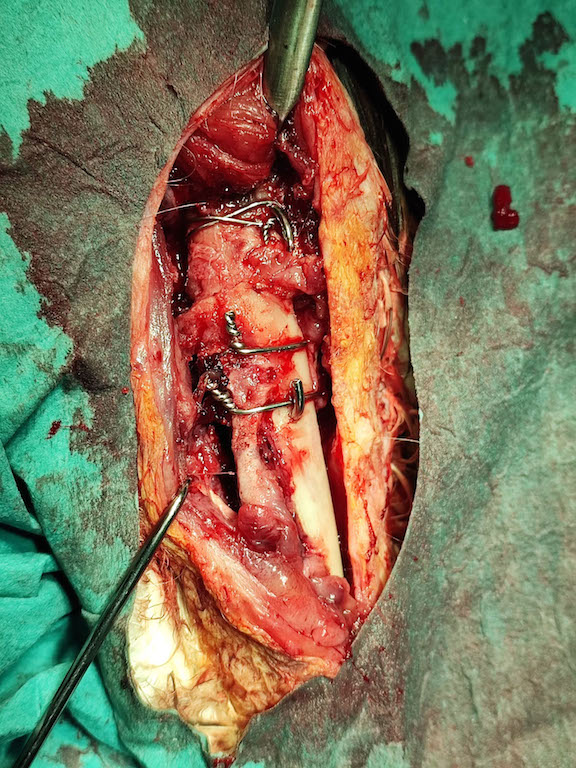

Typ a miesto zlomeniny sa priam nabádalo na použitie operačnej techniky s plastovým kolíkom vloženým do dreňovej dutiny kosti, ktorý sa následne zaistí proti posunutiu a rotácii oceľovými klincami a drátenými slučkami.

Pamatuju zes kdysi na nejakou dlazku nebo neco podobneho pouzival i Shapeplast. Kdybys potreboval, rad ti s necim takovym pomuzu .Treba 3D tiskem, kdybys chtel tak se ozvi. (Mam 3D skener, nekolik tiskaren ruznych technologii...). Zenu zaujaly ty ostre zatocene konce dratu, jestli to pry nedrazdi okolni tkan?